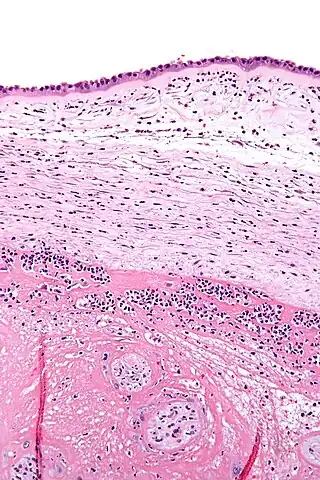

![]() Micrografía mostrando corioamnionitis. Los acúmulos de manchas azules corresponden a células inflamatorias. Tinción hematoxilina-eosina. | ||